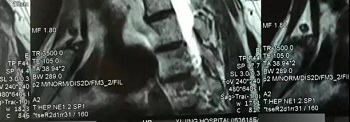

九、翻拍磁共振图像时,因为磁共振片子很大,而且一张片子上有很多图像(如下图),所以,单纯的拍一张片子,因为手机拍摄,像素以及翻拍质量不好,且放大后图像会发虚,细节看不清楚,所以,基本上是没用的,对于医生阅片来说,质量太差,不能获取图片上的有效信息。

十、因此需要将磁共振的一张片子,进行分区域局部放大拍摄,尽可能的将片子上的细节拍摄清楚,将一张磁共振片子进行分区。

十一、将分区的磁共振图像,按顺序进行拍摄,即可获取如下比较有价值的清晰图片

拍摄时,必须要对着片子上的文字对焦, 方向正确,将文字拍摄得清晰可视,保证放大图片后文字依然清晰可见(如下图),尽可能多的保留片子上的信息。